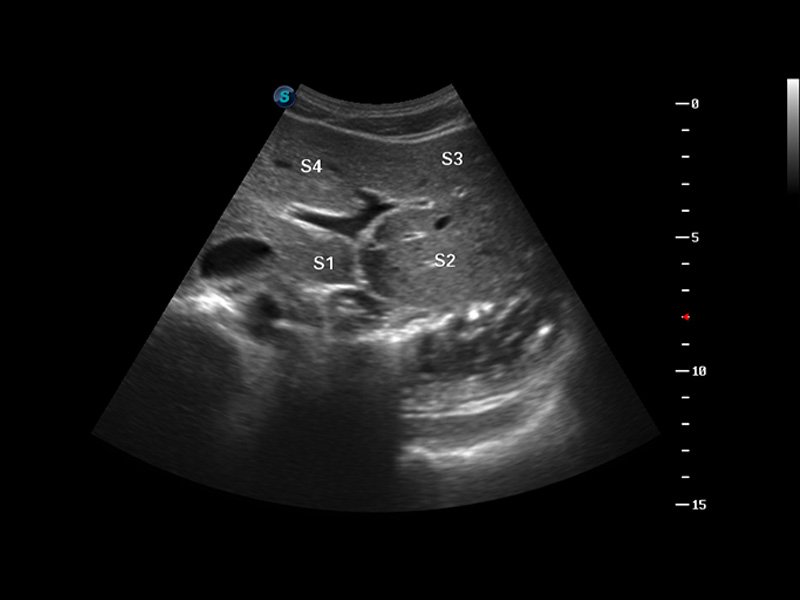

S8 EXP便携式彩色多普勒超声诊断仪是百老汇电子游戏官网研发的高端全身应用型便携彩超。高通道的VIS平台融合可视化(Visual)、智能化(Intelligent)和人性化(Smart)的特点,配以百老汇电子游戏官网自主研发生产的探头大家族,使您能够快速、准确的获得病人信息,提高工作效率的同时减轻疲劳。

μ-Scan微米成像

谐波成像

空间复合成像